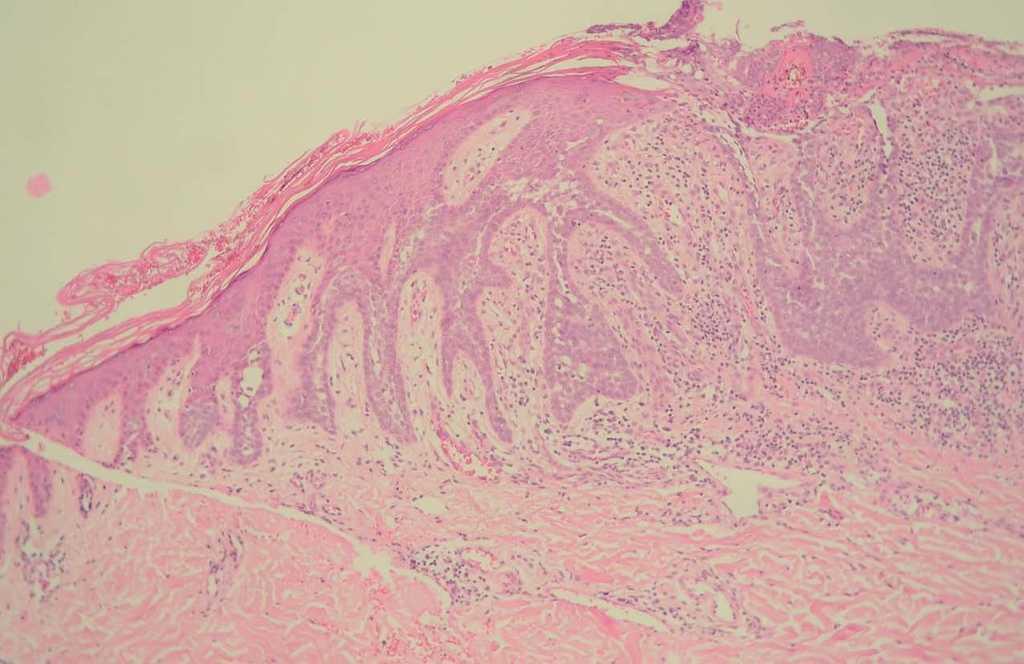

El paciente acudió a consulta por la aparición de tres pápulas de coloración carnosa sobre el nevo sebáceo (fig. 1). Se procedió a la extirpación de estas lesiones y el estudio histológico mostró la aparición de agregados de células basaloides organizados en islotes celulares que fueron diagnosticados de carcinomas basocelulares. En una de ellas, la simetría, el aspecto claramente circunscrito de la lesión y la presencia de una grieta de retracción entre el estroma tumoral y la dermis adyacente planteó la posibilidad de un tricoblastoma, aunque la disposición del tumor con su eje mayor en sentido horizontal, así como el predominio del componente epitelial sobre el estromal entre otros, llevó al diagnóstico final de carcinoma basocelular, aunque con un componente hamartomatoso (fig. 2). En las otras dos lesiones, los islotes de células basaloides que colgaban de la epidermis, así como la asimetría y la ulceración llevaron al diagnóstico de carcinoma basocelular (fig. 3).

Fig. 2.--Proliferación circunscrita de células basaloides con una grieta de retracción entre el estroma tumoral y la dermis. (Hematoxilina-eosina, x 10.)